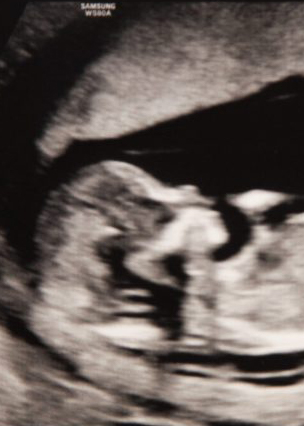

It’s been thirty-one weeks and you are close to sixteen inches long and weigh up to four pounds. You are most active in the evenings, kicking much faster and stronger than I would have imagined. (I asked my doctor at my last appointment if it was possible that you were moving too much. She assured me no.) We love to feel you moving, your father and I.

I spend a lot of time these days imagining you being in the world. We just finished a birthing class that quelled most of my fears about labor, replacing them with knowledge of what to expect and a better understanding of the process. We learned how to recognize early labor, how to breathe, what to expect at home and in the hospital, what will happen right after you’re born. Most helpful for me was the reassurance that my body will know what to do when the time comes—and so will you. This has surprised me again and again over the last seven months: that my body and you have known exactly what to do. My growing belly, your stretches and kicks, the sound of your heartbeat at every appointment: all feel like blessings that have occurred without any active doing on my part. I can only marvel.